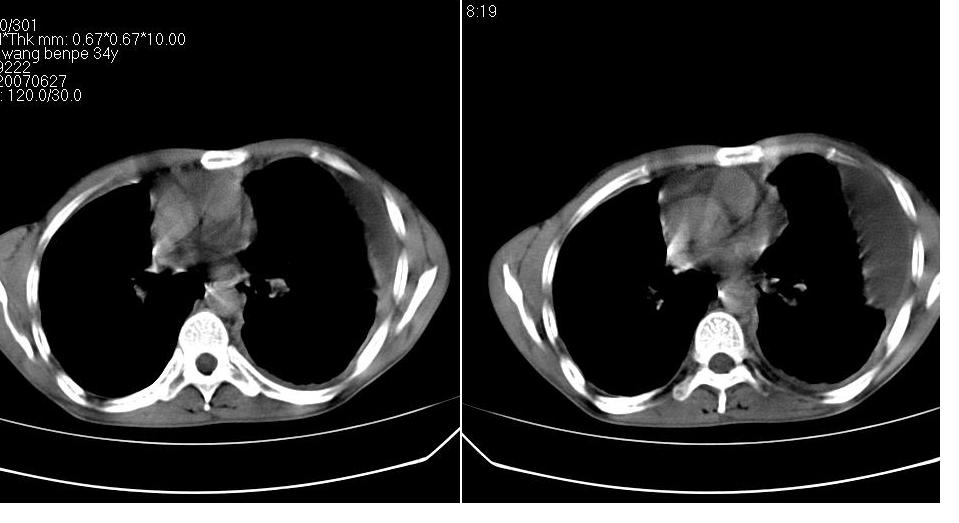

以下是引用苯小孩在2007-6-27 15:09:00的发言:[br]考虑:1、右肺继发性肺结核.2、双侧包裹性积液<胸腔及叶间>3、双侧局部胸膜增厚.[br]建议胸水化验检查.

以下是引用yanghaochen88在2007-6-27 15:08:00的发言:[br]双肺上野散在粟粒状影、包裹性积液、胸膜增厚粘连、叶间积液---tb,至于分型还得结合病史体征细究妥当些。